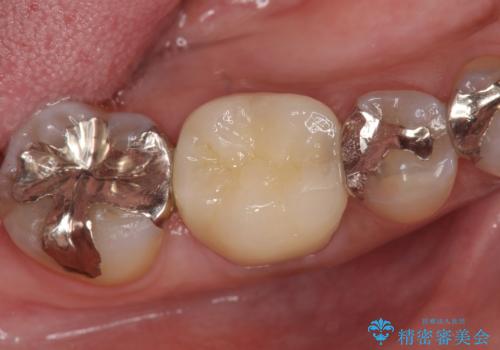

今回用いたオールセラミッククラウンはジルコニアフレームという白い素材の上にセラミックを盛っているため、審美性が非常に高いのが特徴です。

また、ジルコニアは人工ダイヤモンドの材料にも使われているほど高い強度を持っており、そのためオールセラミッククラウンは審美性だけでなく、奥歯やブリッジの補綴も可能とするクラウンです。